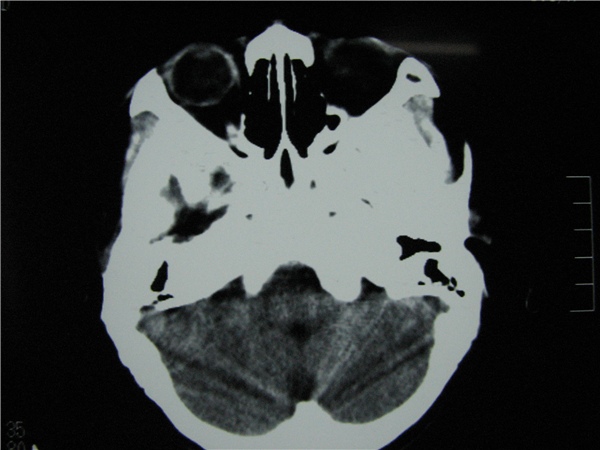

标题: CT20748:M 15Y 头痛,以前有外伤史请老师看看除了囊肿还有别 [打印本页]

标题: CT20748:M 15Y 头痛,以前有外伤史请老师看看除了囊肿还有别

m 15y 头痛,以前有外伤史请老师看看除了囊肿还有别的吗?

蛛网膜囊肿。眼拙,看不出别的,倒是看到了双侧大脑中动脉影,类似“致密动脉征”。

双侧侧裂池和纵裂池近前颅窝蛛网膜囊肿。

不能除外脑穿通畸形

无明显占位及负占位效应,考虑软化灶并脑室穿通畸形囊肿、局限性脑萎缩

蛛网膜囊肿,不能除外脑穿通畸形,支持。